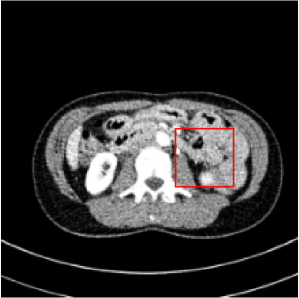

| Image | GT ROI | LDCT (0.7675) | REC (0.8756) | NAC (0.8802) | SSWL (0.8884) |

Figs. 3 and 4 demonstrate precise removal of noise from whole scans as well as specific regions of interest (ROIs), proving the effectiveness of our model over baseline architectures and other self-supervised tasks. As shown, both the RVAE and SSWL are able to quantitatively and qualitatively outperform their respective counterparts.